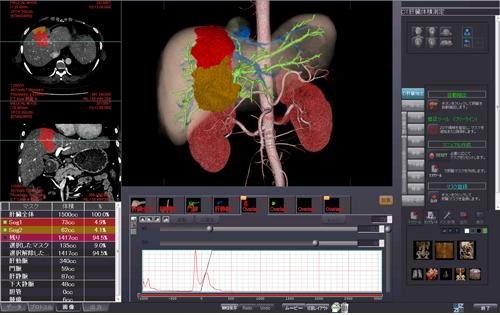

肝臓実質全体や任意の区域の体積計測,および血管支配領域の推定や門脈,静脈,動脈血管,腫瘍の位置関係の観察に有用です。PhyZiodynamicsの技術を利用した非常に精度の高いレジストレーションおよび抽出を行います。術前の切除領域のシミュレーションにも有効。ガイドに沿ったワークフローで抽出から分割,測定まで容易に行えます。